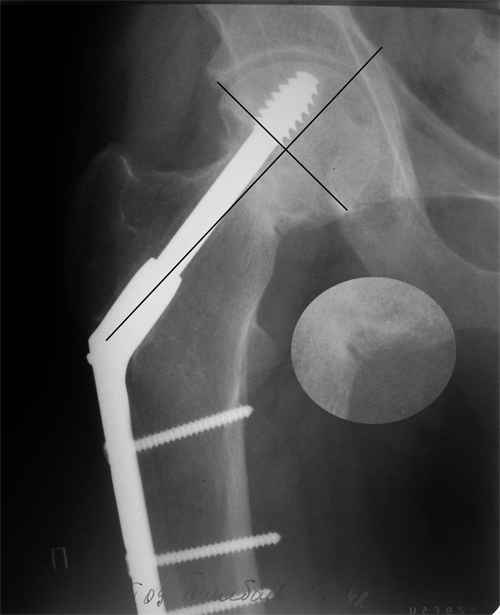

Больной Т. 1966 г.р.Травма 28.06.2007. Прооперирован в г. Бишкек, Оп: Остеосинтез правого бедра системой DHS. В последующем беспокоили периодические боли в правом тазобедренном суставе с иррадиацией в коленный сустав в область передней поверхности правого бедра. Лечился амбулаторно с незначительным эффектом. В 07.04.2008 по 08.05.2008 года лечился в госпитале ГУВД и СО в стационаре с Срастающийся перелом шейки правого бедра в условиях фиксации системой DHS – боли уменьшились.Боли обострились 03.02.2009 внезапно, госпитализирован. Результат - Псевдоартроз шейки правого бедра (имеются косвенные признаки разрушения спонгиозной части головки бедра)Планируется - Работает милиционером. Имеющийся опыт протезирования у данной категории во всех случаях в ближайшее время заканчивался дисквалификацией. Работоспособный возраст (43 года).Наиболее приемлемым и реальным методом лечения предполагается: Удаление конструкций из бедра. Заполнение полости от винта монолитным аутотрансплантатом из крыла (крылев) подвздошной кости. Медиализация большого вертела. Предполагаемый период нетрудоспособности 3-4 мес.

На более раннем снимке репозиция была, мягко говоря, далека от идеальной. Плюс перелом шейки слишком проксимальный для фиксации одном винтом. Неудача тут закономерный исход.

Но в данном случае DHS сыграл как имплант с угловой стабильностью, что привело к прорезыванию импланта в верхнем сегменте головки. Отсутствие трехточечной опоры и длинный имплант увеличивают нестабильность в шейке.